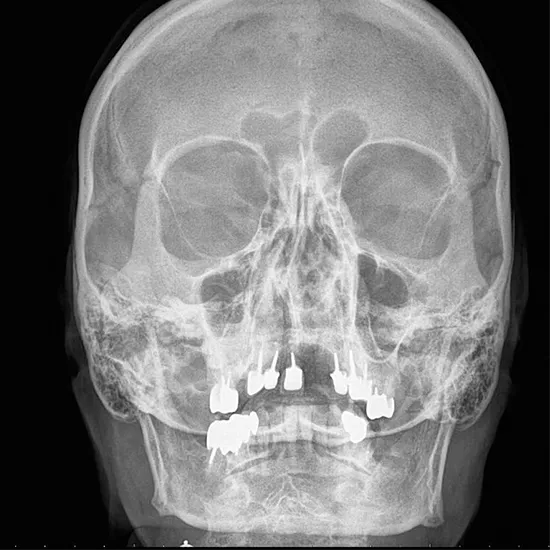

X-Ray Nasal Bone AP/LAT

X-rays of the nasal bone (AP view) assess whether the bone is intact or broken and if the sinuses are clean or inflamed. This is done for several nose treatments. Visit a medic if you have any of these symptoms as soon as possible.

This test is primarily used to examine the sinuses and nasal bone structure so that your doctor can evaluate whether your nasal bone is intact and formulate an appropriate treatment plan in the event of a bacterial or fungal infection.